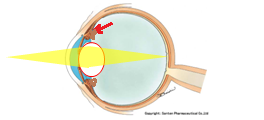

今日は水晶体亜脱臼による緑内障発作の患者様がいらっしゃり、お昼休みに緊急手術をさせて頂きました。